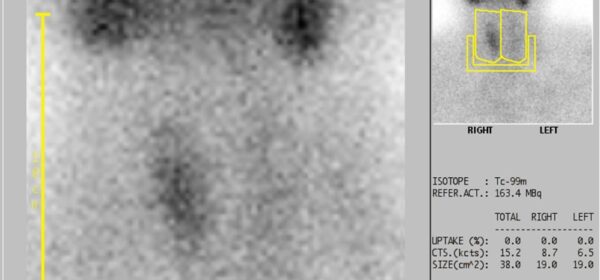

Thyroid scintigraphy

Scintigraphy